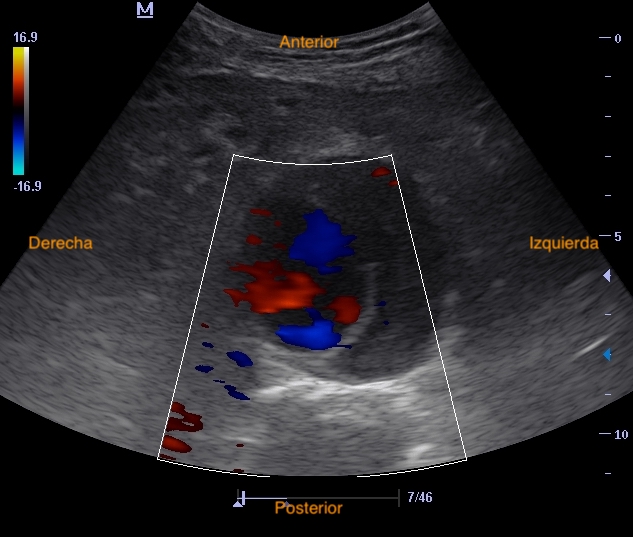

Hallazgos ecográficos

Realizamos eco en consulta donde se aprecia el AAA de 5,6 cm con trombo mural similar a previo, sin signos de rotura.

Aneurisma aórtico abdominal infrarrenal de > 5,5 cm con trombo intramural en su interior.